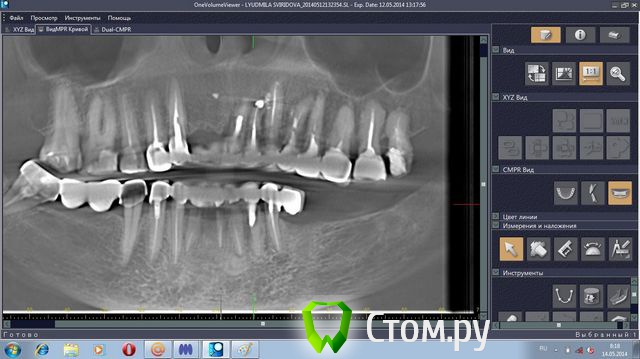

stradalitca Опубликовано 18 мая, 2014 Поделиться Опубликовано 18 мая, 2014 Здравствуйте! у меня проблема такая. за последние 4 года мне удалили нижний центральный зубик (киста была), пролечили каналы в нижних зубах. Поставили мост с металлокерамики. Он простоял некоторое время, а потом( год-два) просто стал качаться. Его раза три сажали заново на цемент( прошлым летом). в итоге, пошла в другую клинику. Мост ещё раз сняли( он держался на честном слове). Оказалось, что пятёрка снизу слева пробита вкладкой. Зуб удалили. На сдедующий день обточили ещё зубы некоторые и сняли слепок под новые пару вкладок. через неделю поставили на цемент( сразу на цемент, без времянки)НОВЫЙ мост. Это было в конце декабря. Через две недели десну разнесло и прищлось резать, выпускать гной( надрез примерно под тройкой слева). Сейчас опять явный свищ примерно под 3-4 нижними слева.Сделали рентген - оказалось, что тройка имеет два корня и она пробита вкладкой. Теперь даже не знаю что делать. Просто резать десну и опять чистить? Врач говорит, что надо снять мост и удалить тройку. Другой врач говорит, что тройку может и можно спасти, надо снять мост, убрать вкладку и смотреть, что с тройкой. На прошлой неделе сделала объёмный рентген. Сама неделю копалась в программе, разглядывя свою нижнюю челюсть. мне показалось, что там маячит какой-то остаток корня шестёрки слева( мне его сто лет назад удаляли). Пожалуйста, подскажите, что делать? какие перспективы и варианты есть на мои нижние зубы?Заранее большое спасибо за все ваши ответы и мнения.Скриншоты с программы 3D прилагаю.или может надо мост снять, выдернуть тройку слева и поставить металлопластмассу?( верхние зубы тоже штук 8 слитно металлокерамика, ставили первый паз отдновременнно нижние и верхние) Ссылка на комментарий

sydnik Опубликовано 18 мая, 2014 Поделиться Опубликовано 18 мая, 2014 Здравствуйте! скриншоты не очень информативные,носкажу наверняка -3-ку на удаление, разрезами десны и чистками ничего не добьетесь.корня шестерки я не вижу.металлопластмассу не рекомендовал бы( синеет,откалывается,стирается,эстетика хромает на обе ноги). Мост расшатался из-за отсутствия зубов слева, в результате чего вся нагрузка ушла на передние зубы имплантацию не рассматривали?все ли хорошо с верхним мостом? пока все Ссылка на комментарий

stradalitca Опубликовано 19 мая, 2014 Автор Поделиться Опубликовано 19 мая, 2014 а насчёт верхних зубов - маме кажется. что мост не плотно стоит. И подозревает, что может он сдвинулся в момент снятия слепка для нижней челюсти? А на снимке "вид сбоку осколка?" я не могу понять, может это пятнышко( я его замеряла в программе - 1 см длиной)-это след от удалённой пятёрки? её удалили в декабре. Ещё напрягает светлое пятно под двойкой и темноватое под четвёркой. И ещё есть у меня вопрос - сколько имплантов можно ставить за один раз( коли уж местный наркоз применять). и как долго ждать до постановки на них коронок? спасибо вам заранее за ответ. Ссылка на комментарий